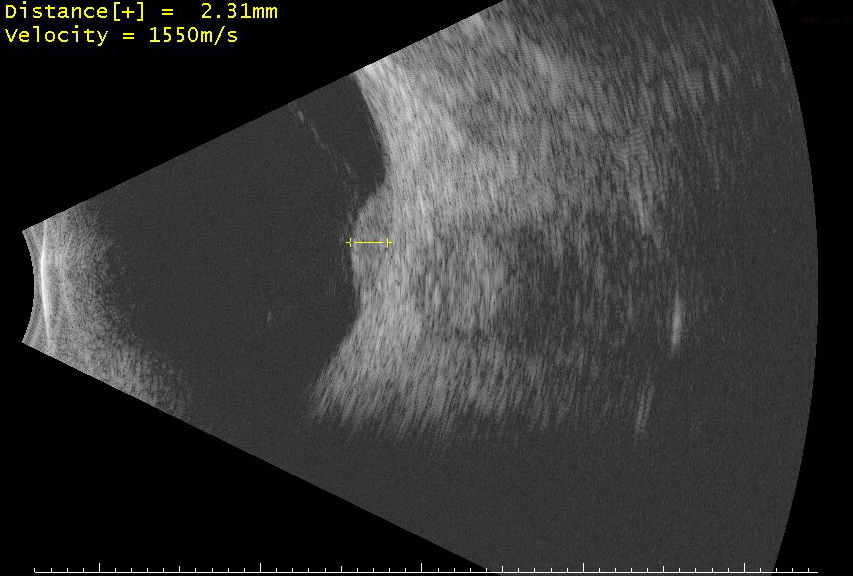

Ocular toxocariasis is caused by infection with the second-stage larvae of the roundworms Toxocara canis or Toxocara cati. The infection can have three primary presentations: 1) chronic endophthalmitis, 2) localized granuloma, and 3) peripheral granuloma. These photographs show a classic localized granuloma located over the optic nerve. Also shown are the appearance of the granuloma on B-scan echography and optical coherence tomography (OCT).

Appearance of the granuloma on B-scan echography